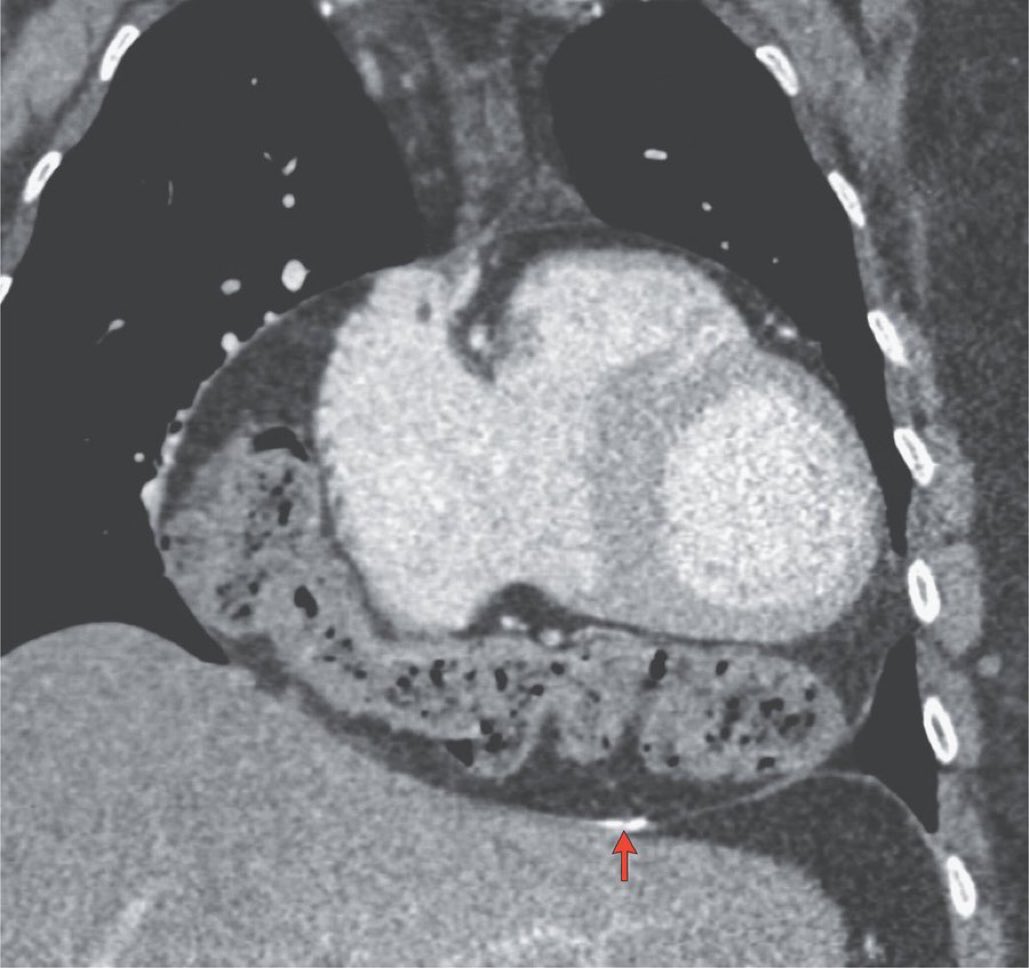

Congrats to Olive View UCLA ❤️bound Devon Terraciano for presenting a 😨 case of ICI myocarditis with biomarker rebound despite steroids, immunosuppression. Many❓on outpt tx strategies which requires further 🔍 🙏 Ashley Stein-Merlob, MD PhD & our CMY & onc MemorialCare for their amazing care

🙏UCI Cardiology MemorialCare & fellows for having Ashley Stein-Merlob, MD PhD Devon Terraciano et al attend your presentation of a #cardioonc challenging case of ICI myocarditis. Awareness, education & collab at all healthcare systems are critical to ⏫⏫ recognition & early intervention!